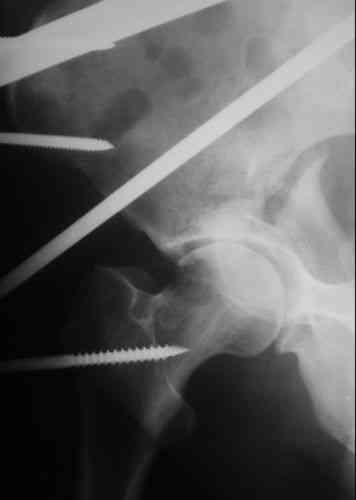

Пациентка 38 лет. В результате ДТП 02.09.06 получила поперечный перелом правой вертлужной впадины, центральный вывих правого бедра, разрыв правого крестцово-подвздошного сустава.

В одной из районных больниц вывих устранен, наложена система вытяжения по оси бедра и за вертельную область. Спустя 2 недели выполнен ВЧКО модулем "таз-бедро". Учитывая возраст пациентки и остаточный диастаз в области свода вертлужной впадины предполагается демонтаж аппарата, открытая репозиция и внутренний МОС вертлужной впадины через внутритазовый доступ.

в ближайшее время лучше выкрутить стержень из вертлужной области